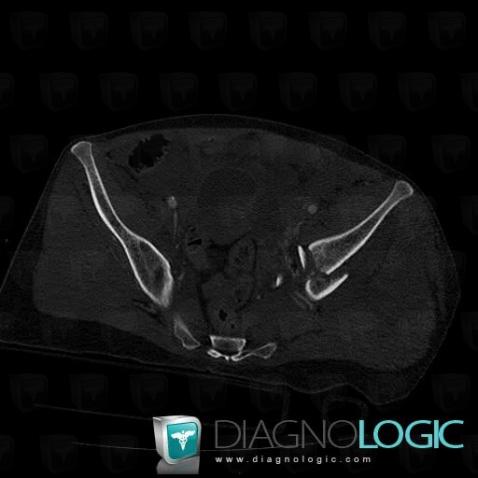

Fracture, Ilium, CT

- Diagnosis Fracture, Location(s) Ilium, with gamuts